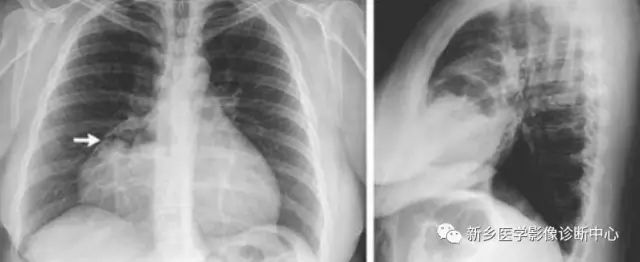

[影像描述]

CT:贲门级部分胃体组织通过食管裂孔进入胸腔内,位于膈上,其上段食管明显扩张。

CT:食管裂孔疝以食管下端纵隔内有疝囊检出为直接征象。疝囊以假肿块样改变为特征,可有软组织密度肿块,也可表现为囊性液体密度影,部分疝囊以食管下端扩张改变为影像表现,经食管裂孔向膈下胃腔延续为主要特点。疝囊外壁光整,内壁可呈锯齿状,可见胃黏膜影像。胃壁充盈好则厚度较薄,疝囊带状管腔扩张样改变,内有潴留食物;充盈不佳者囊壁较厚,表现为软组织团块样影,内有少量液体或气体影。采用CT增强扫描,胃壁与疝囊囊壁均匀一致。